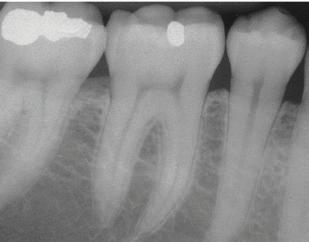

The culture of the hygiene program at Falcon Park Dental Group is proactive. We will quit watching and start treating. Our providers will link periodontal conditions to medical conditions and will refer to primary care physicians for unresolved inflammation. We will help our patients understand that bone loss is not a symptom; it is a RESULT. When we see bone loss on an x-ray, it is more destructive than it appears. We will also commit to using salivary diagnostics when indicated. We have committed ourselves to helping our patients understand that we must treat periodontal inflammation before it is too late.

Recognizing and treating periodontal disease in its earliest stages results in better patient outcomes and has been shown to positively affect the long term whole-body health of patients. Early disease recognition and management can only be accomplished by performing a thorough comprehensive exam which includes, but is not limited to, an oral cancer exam, full mouth pocket charting, and radiographs with a clear view of the interdental crestal bone. As clinicians, we know radiographic bone loss, no matter how minor, is a result of a long-standing infection in periodontal tissue.

Visually show bone loss through the patient’s own X-rays and/or the educational poster